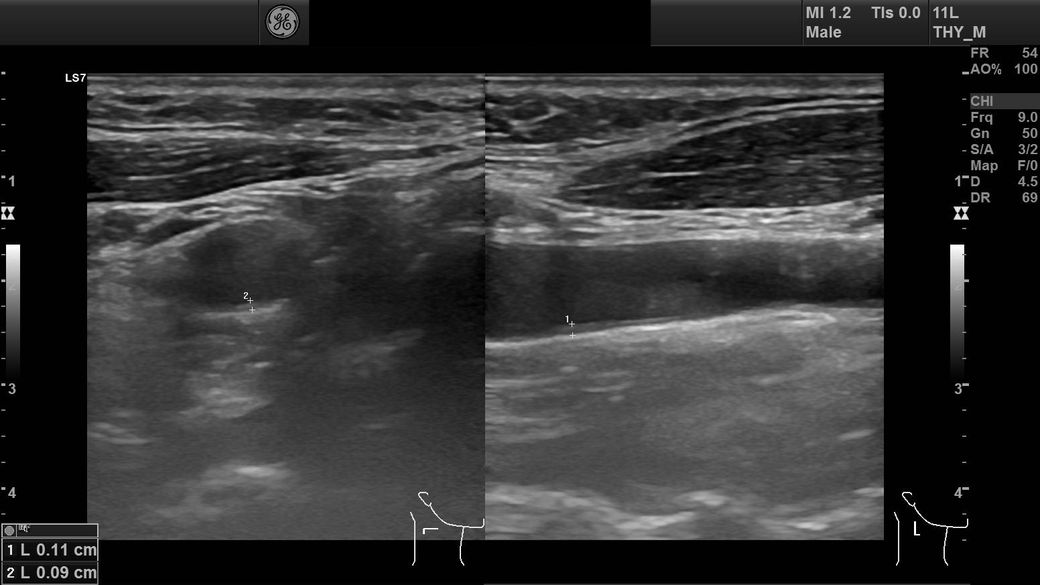

경부초음파사진 결과 사진 질문드립니다

임파선이 부어서 초음파를 찍었는데

어떤 사진인지는 모르겠는데 혈관이 왼쪽에 비해 오른쪽이 좁다고 하셨는데 이게 큰 문제가 있는건가요?

• 1번 째 사진

혈관이 좁다고 했다면 경동맥을 말하는 것 같습니다

경동맥의 경우 2D로 관찰을 했을 때 내강이 절반이 되더라고 전체면적으로 봤을 떄는 많이 좁아진 것이 아니니

크게 걱정하지 않으셔도 됩니다

판독기록에 어느 정도 좋아졌는지 확인을 해보세요